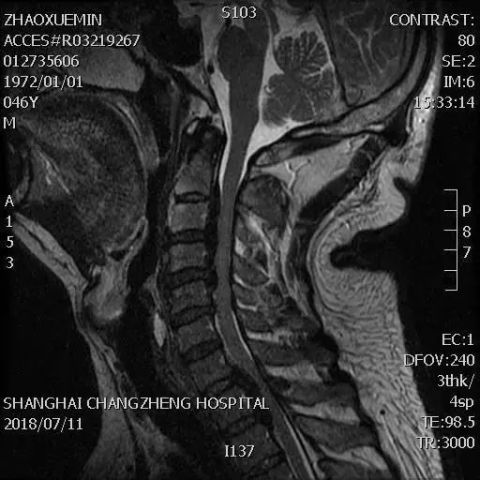

十五年前,他千里迢迢到上海长征医院做手术;二

如此长的后纵韧带骨化,只有他们才敢直接手术

颈椎后纵韧带骨化症是指因颈椎的后纵韧带发生骨化,从而压迫脊髓和神经根,产生肢体的感觉和运动障碍及内脏

颈椎后纵韧带骨化脊髓受压的磁共振表现及临床意义,目的:进一步认识颈椎后纵韧带骨化(O P L L)致髓受压